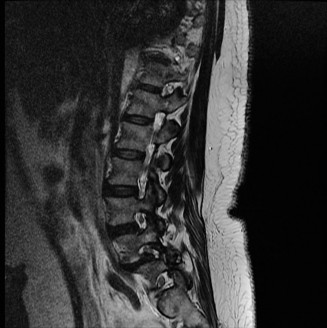

The diagnostic imaging workup for this patient spanned his initial presentation at age 15 and his subsequent return at age 20, providing a textbook illustration of the natural history of untreated isthmic spondylolysis. During his initial visit, standard weight-bearing anteroposterior (AP), lateral, and bilateral oblique radiographs of the lumbar spine were obtained. The lateral radiograph demonstrated a normal lumbar lordosis and preserved L5-S1 disc space height, with no evidence of anterior translation (spondylolisthesis). However, the oblique radiographs revealed the pathognomonic "collar on the Scotty dog" sign. The "Scotty dog" represents the posterior elements of the vertebra, where the nose is the transverse process, the eye is the pedicle, the front leg is the inferior articular process, and the neck is the pars interarticularis. A radiolucent line across the neck confirmed the presence of bilateral L5 pars defects.

Had the patient been compliant with follow-up during his initial presentation, advanced imaging such as a Single Photon Emission Computed Tomography (SPECT) scan or a Magnetic Resonance Imaging (MRI) scan with Short Tau Inversion Recovery (STIR) sequences would have been indicated. These modalities are highly sensitive for detecting acute stress reactions and marrow edema in the pars interarticularis before a frank fracture line becomes visible on plain radiographs. An MRI at that early stage would have likely shown high signal intensity in the bilateral L5 pars regions on T2-weighted STIR images, confirming an active, metabolically "hot" lesion that possessed a high potential for healing with rigid bracing.

Upon his return five years later, the imaging profile was drastically different. Standing lateral radiographs now revealed a Meyerding Grade 2 spondylolisthesis at L5-S1, indicating that the L5 vertebral body had translated anteriorly by 25% to 50% over the sacral promontory. Furthermore, there was a noticeable collapse of the L5-S1 intervertebral disc space, signifying advanced degenerative changes secondary to the altered biomechanics and chronic instability. We also meticulously measured the patient's spinopelvic parameters on a standing 36-inch scoliosis cassette. His Pelvic Incidence (PI) was measured at 65 degrees (high), which mathematically dictates a higher Sacral Slope (SS) and Pelvic Tilt (PT). A high PI is a known biomechanical risk factor for the progression of spondylolisthesis, as it creates a steeper lumbosacral shear angle, placing immense anterior translational force across the compromised L5-S1 segment.

Clinical & Radiographic Imaging Archive